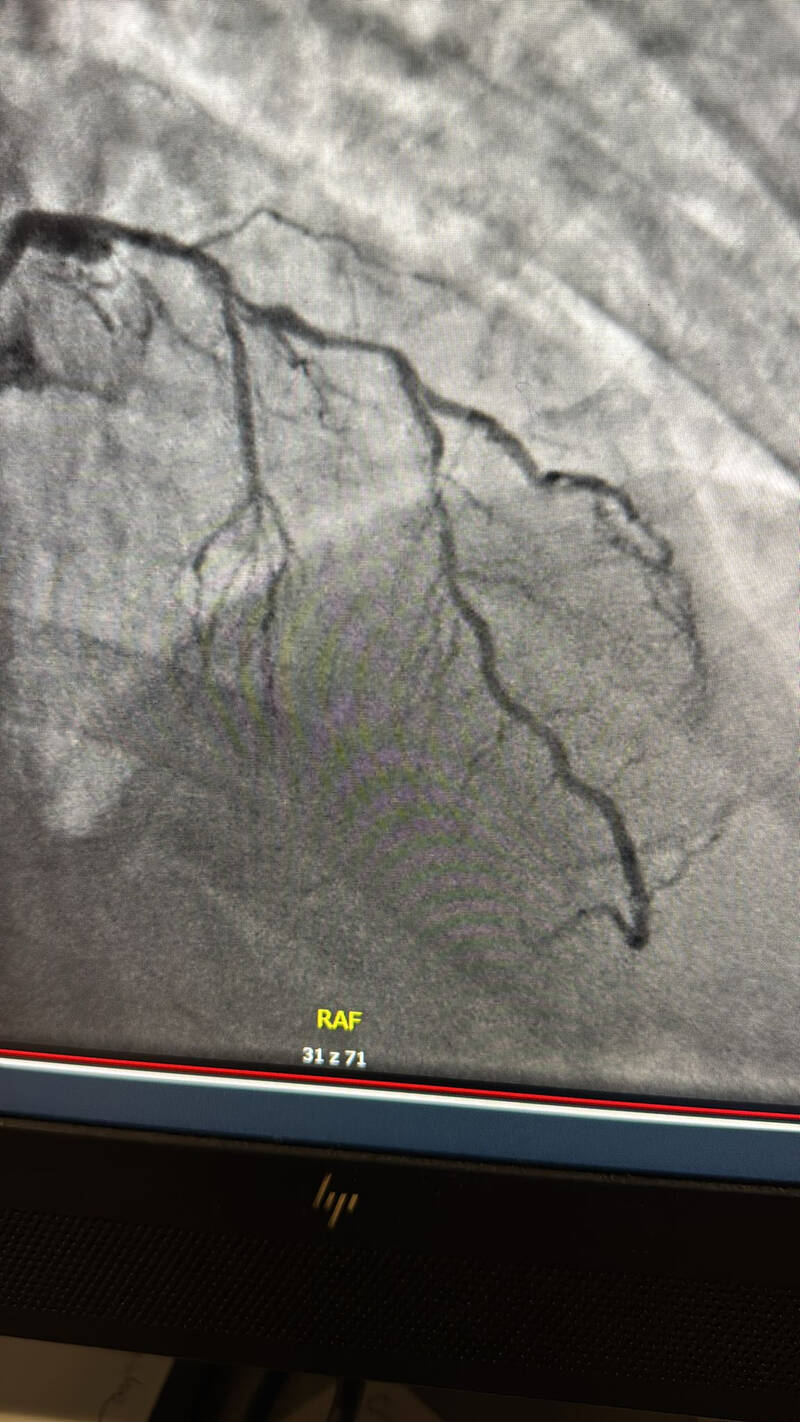

mloz6989.jpg

Obrazowanie angiograficzne naczyń wieńcowych w czasie rzeczywistym

Obrazowanie NIRs – zaawansowana technologia, pozwalająca na precyzyjną wizualizację naczyń wieńcowych w czasie rzeczywistym.